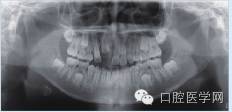

辅助检查:全颌曲面断层片显示左侧下颌骨体部可见类圆形高密度影,周围可见低密度影环绕(图1a);CT显示:左侧下颌骨体部呈膨胀性骨质改变,局部骨皮质变薄,内伴高密度骨质硬化影,边界尚清晰,周围软组织肿胀(图1b)。

图1 a:全颌曲面断层片;b:CT影像